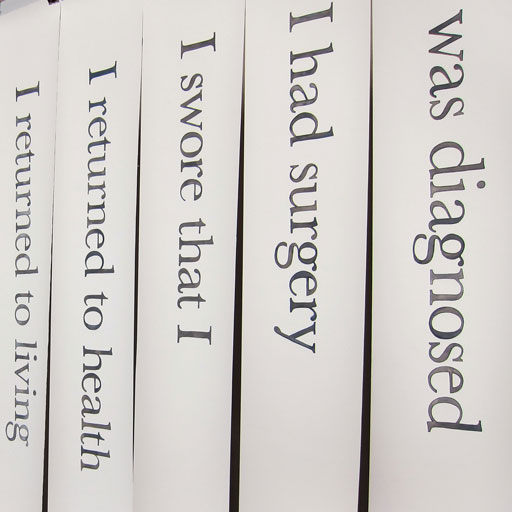

how does it feel to be a patient?